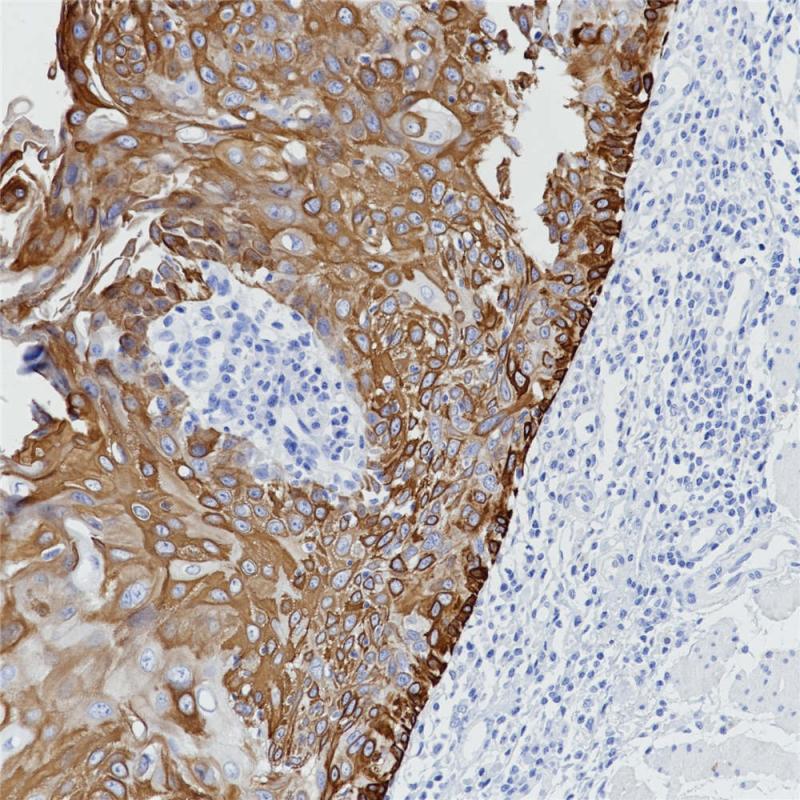

乳腺癌TRPS1(BP6231)染色

TRPS1是一种转录因子,最初发现在毛鼻指骨综合征(一种颅面和骨骼畸形综合征)中发生突变。TRPS1识别GATA序列,抑制其他GATA因子的激活潜能。TRPS1在乳腺癌、宫颈癌、食管上皮中高表达。在病理诊断中,TRPS1是一种敏感、特异的乳腺癌标志物。